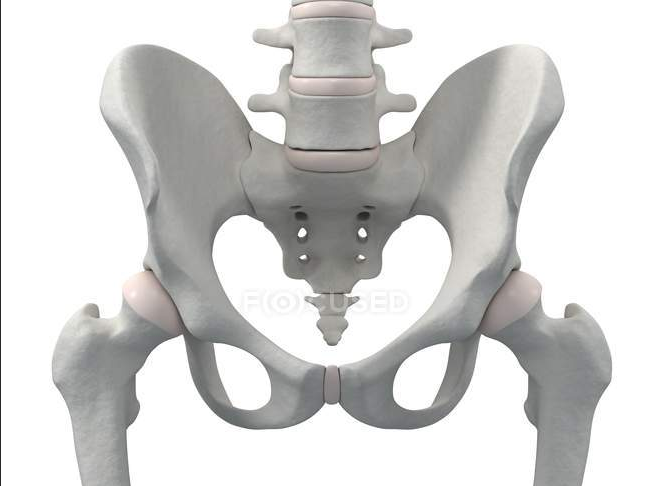

Die Haltemuskeln an den Querfortsätzen der Wirbelkörper stabilisieren die Wirbelsäule, machen die Feinabstimmung und führen kleine Bewegungen (Rotation, Seitneigung) aus. Die Hals- und obere Brustwirbelsäule ist das Punctum fixum bei Bewegungen im Schultergürtel und dem Schultergelenk. Im Gegensatz zum Beckengürtel, der knöchern geschlossen ist und somit für Stabilität in der unteren Körperhälfte sorgt, ist der Schultergürtel zwischen Schulterblatt und Hals-/Brustwirbelsäule offen und wird muskulär geschlossen, was eine Drehung des Schulterblattes ermöglicht und somit die Bewegungsfreiheit im Schultergelenk deutlich erhöht. Bei Überkopfarbeiten oder manuelle Arbeiten ohne aufgelegte Arme muss diese Muskulatur die Stabilität am Körperstamm leisten und ermüdet bei längerem Gebrauch (> 2–3 Stunden). Übermüdung ist immer mit Verkürzung (Schutzmechanismus der Muskeln) und Verspannung verbunden.